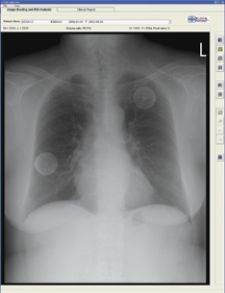

Although results vary, developers of EDDA Technology believe CAD for lung is clinically viable. The company released its FDA-cleared IQQA-Chest software V2.0 for enterprise CAD solution for digital X-ray on November 17, 2006. The solution offers real-time interactive diagnostic analysis of digital chest X-rays using a comprehensive set of tools to support radiologists in their identification, confirmation and quantification of lung nodules. According to the maker, it has clinically demonstrated an ability to improve radiologists’ detection of small lung nodules (5-15mm) up to 85 percent.